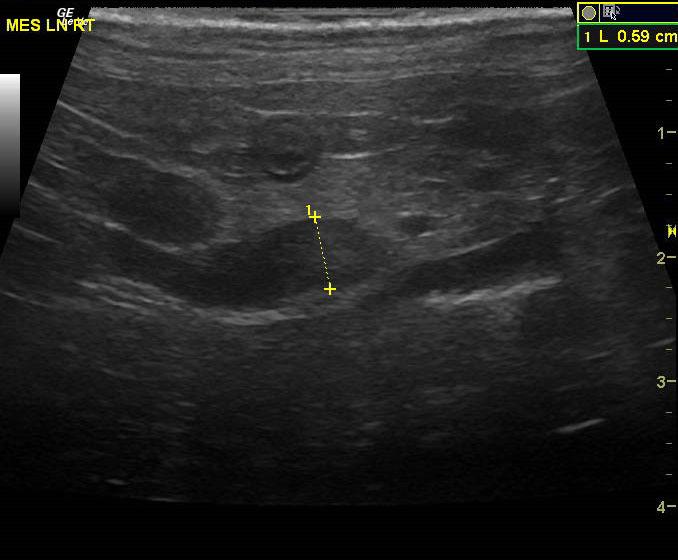

An 18-year-old MN DMH was presented for evaluation of intermittent vomiting and anorexia. A possible abdominal mass was present on abdominal palpation. 1+ calcium oxalate crystals were present on urinalysis. Abnormalities on CBC and serum biochemistry were leukocytosis and hypoproteinemia. T4 was within normal range. Radiographs were within normal limits